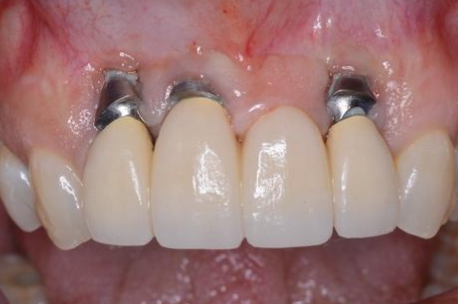

What are the consequences of having an incorrect buccal/lingual implant position?

Cosmetic problems

Hygiene problems

Oral comfort problems

Increased risk of failing implant